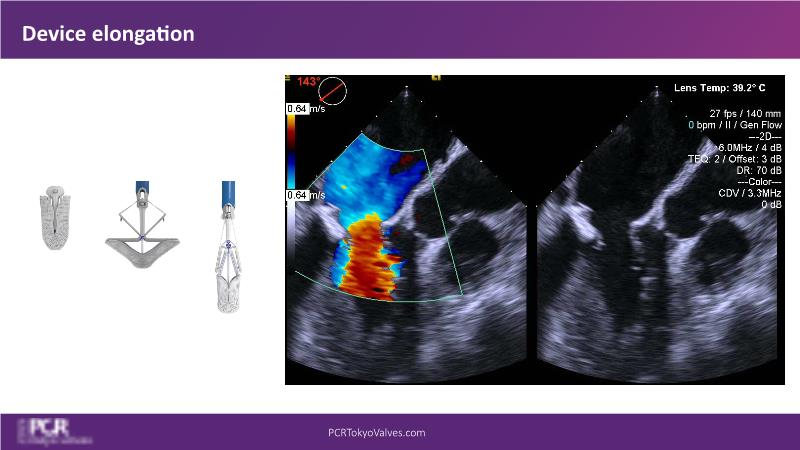

Watch this session to get an overview of a new TEER device, follow the step-by-step procedure related to initial experiences with this device for a Japanese patient with degenerative mitral regurgitation, learn about the latest data from RCT and registries, and follow discussions of challenging TEER cases!

- To understand how novel TEER device provides new possibilities in TEER

- To learn procedural step-by-step of novel device